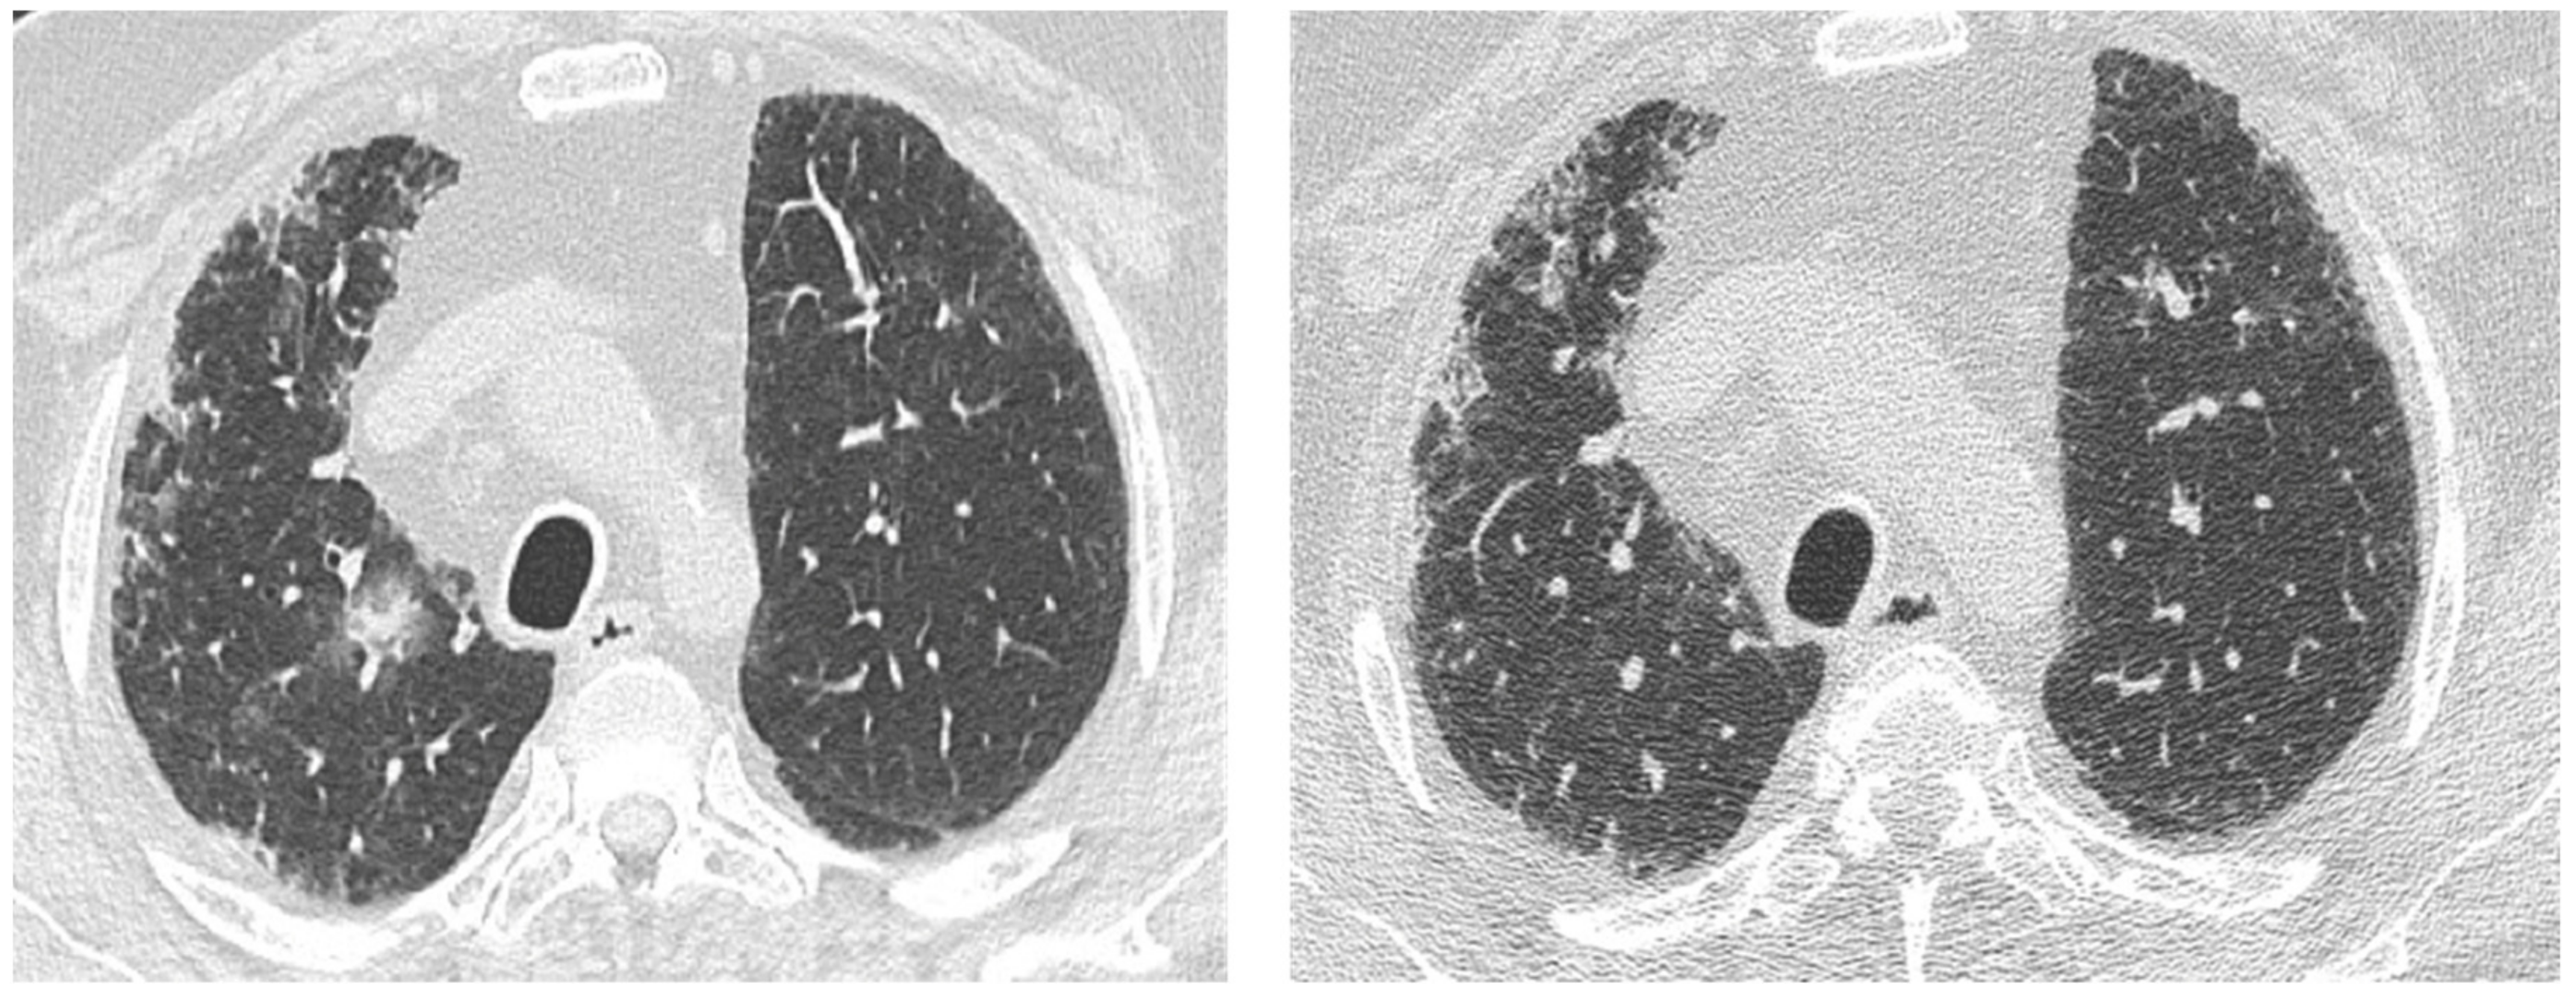

| Acute | Infections | Mycobacterium species | Peripheral mass-like lesion/subpleural nodules/segmental or lobar coalescent consolidation with or without necrotising cavitation. |

| Pneumocystis jirovecii | Ground glass opacity/no change from the baseline in a clinic context of infection. | ||

| Aspergillus | Fungal fronds in a pre-existing cavity in early stages. Subsequent coalescence of the cavity (air crescent sign). | ||